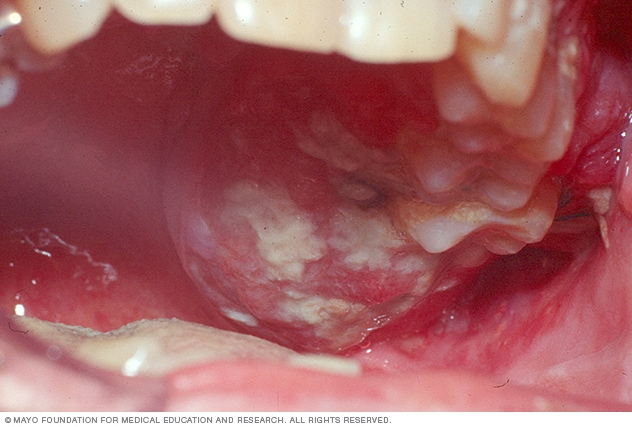

- Red and white patches on the mouth or lips